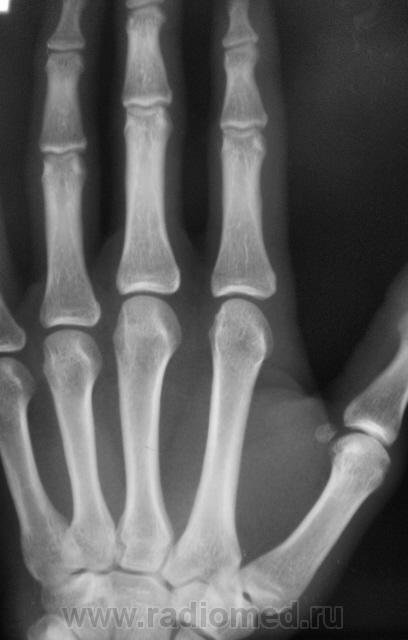

Травма. Пациент направлен на рентгенографию 2 пальца.

Костно-травматических изменений не вижу

Вот это прикол. Настоящая головоломка !!! это инородное тело в области мед края головки осн фаланги 2 пальца.

Ну, не знаю. я тоже ничего не вижу. А тонюсенькая полосочка может быть и артефактом.

По всей видимости, норму надо писать?

Валентин Львович, вы ж укажите, где локальная болезненность. Может перелом основания осн. фаланги?

??? Головка ср.ф. какая-то скошенная, но деструктивн. изм., повреждений не вижу.

Меня тоже смутила форма головки фаланги.